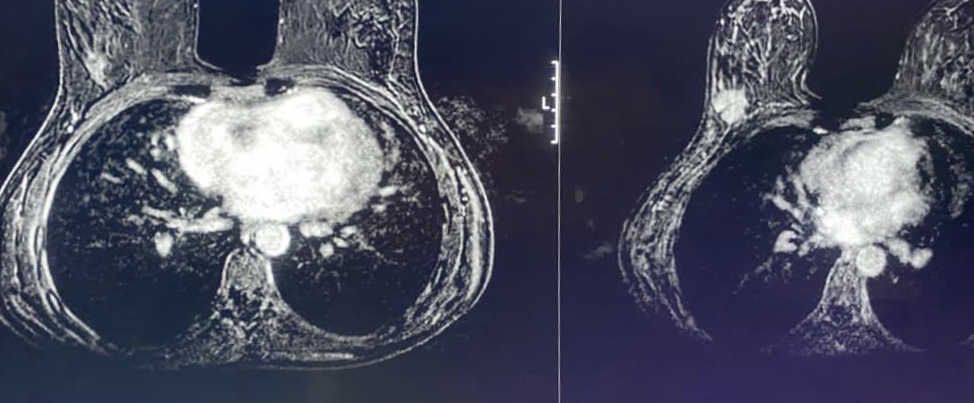

So far, all of my conversations with the oncology team have been with Tom present, as my official note-taker, and then afterwards repeat back to me what they have said. I really do have the memory of a goldfish when it comes to my consultations, no matter how hard I try, I can’t seem to retain correctly what they said to me. Tom happened to be out the next day when Hannah called back – what followed was a very confusing conversation that I was then unable to recall as soon as I hung up. Hannah said that I had been discussed at their multidisciplinary team meeting (MDT) that morning. Their MDT would have been attended by oncologists, surgeons, radiologists along with all the other members of the team, it’s a good approach for making clinical decisions due to everyone from different specialties being able to contribute. The outcome from the meeting was that I should continue with my final round of chemotherapy. I couldn’t understand why, as the tumour seemed to be growing and surely that meant that the new drugs were not working as well as the previous ones? Hannah tried to explain that the MRI showed an overall decrease in tumour volume, when comparing the images from May and this week, and therefore I was responding to treatment. Hannah was reading out a radiology report which included lots of confusing phrases like “the tumour is showing a type 1 curve” and “complete resolution of the tumour” – sounds like I am cured?!

After speaking to Melissa, she explained to me that the decision from the MDT was based upon my last MRI scan report, which showed that the tumour had reduced in volume by over 50%, when compared to the first scan back in May. Apparently MRI is the gold-standard for measuring tumors as it can measure volume, whereas the ultrasound scan is much more subjective to operator and only measures in two dimensions. Panic over – tumour apparently not growing. Sadly must complete my final round of chemotherapy, that’ll teach me for getting my hopes up! Warning, explicit content below…